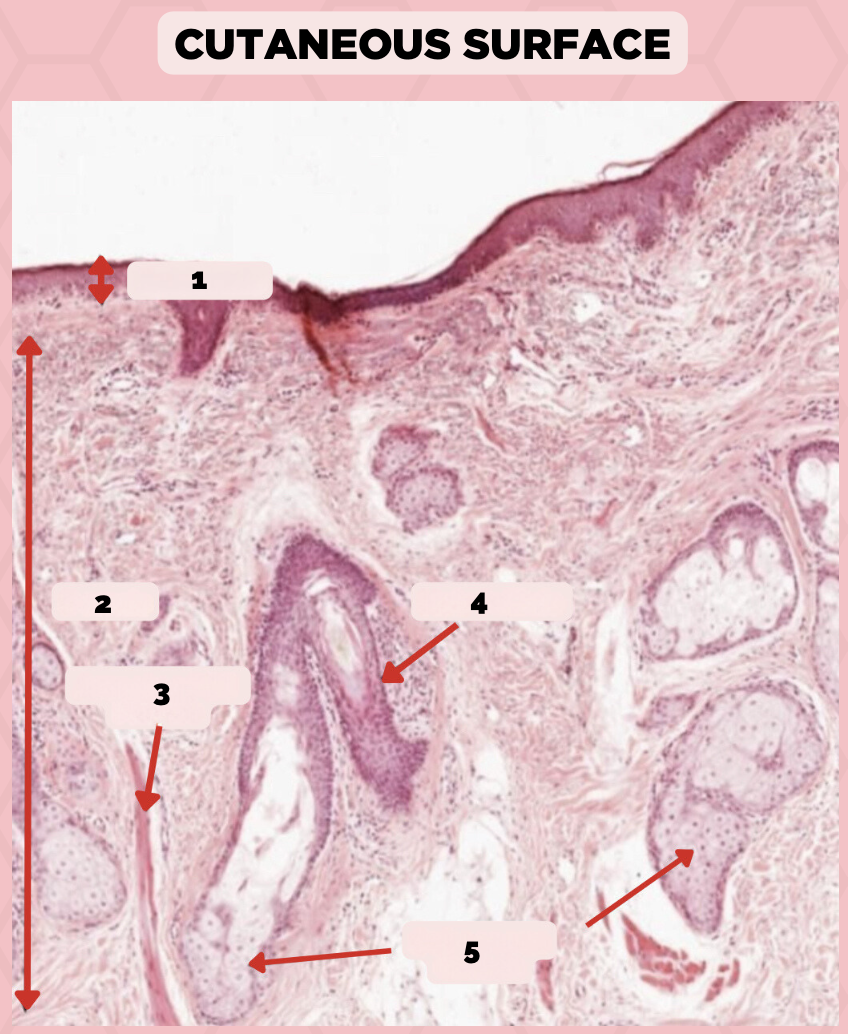

Lip

What specimen is being showed in the picture?

Epidermis

Identify the structure labeled as 1.

Dermis

Identify the structure labeled as 2.

Arrector Pilli Muscle

Identify the structure labeled as 3.

Hair Follicle

Identify the structure labeled as 4.

Sebaceous Glands

Identify the structure labeled as 5.